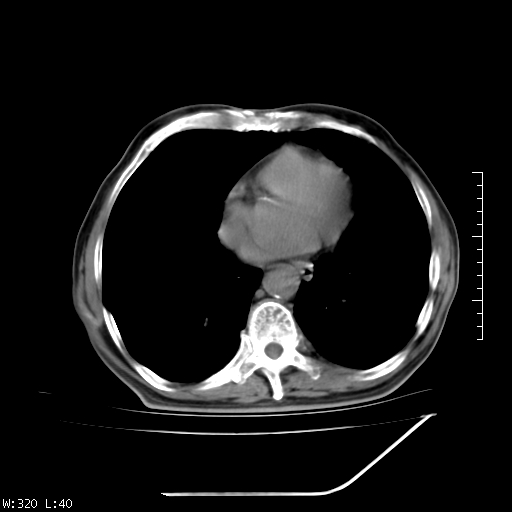

标题: CT23994:男、72、咳嗽、气短两月余,近来消瘦。 [打印本页]

标题: CT23994:男、72、咳嗽、气短两月余,近来消瘦。

右上肺实变,与胸膜关系密切,右肺容积缩小,隆突下淋巴结增大,考虑1 肺结核 2 肺癌

右上肺大片状密度增高影,与胸膜关系密切,内见低密度透亮影,胸膜下可见三角形不张影,左下肺沿支气管走形结节影,纵膈内淋巴结显示。考虑结核并疤痕性不张可能性大,建议穿刺活检,排除肺泡癌。